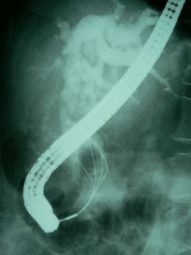

Cálculo gigante ERCP

Envíado por Dr. Carlos Miguel Zavaleta Consuegra